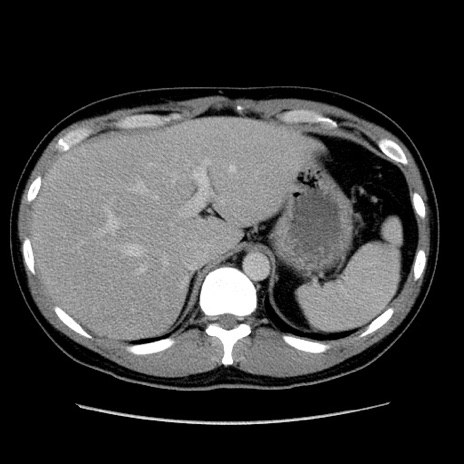

冠状断像

【症例】30歳代男性

【主訴】腹痛、嘔吐

【現病歴】昨晩から突然の腹痛あり、その後嘔吐、軟便も出現。腹痛が改善しないため救急搬送となる。2日前にしめ鯖の食事歴あり。

【身体所見】意識清明、苦悶様、BP 135/90mmHg、BT 35.7℃、腹部:平坦、やや硬、心窩部〜臍部に自発痛、圧痛あり、筋性防御+、反跳痛-

【データ】WBC 8100、CRP 0.57